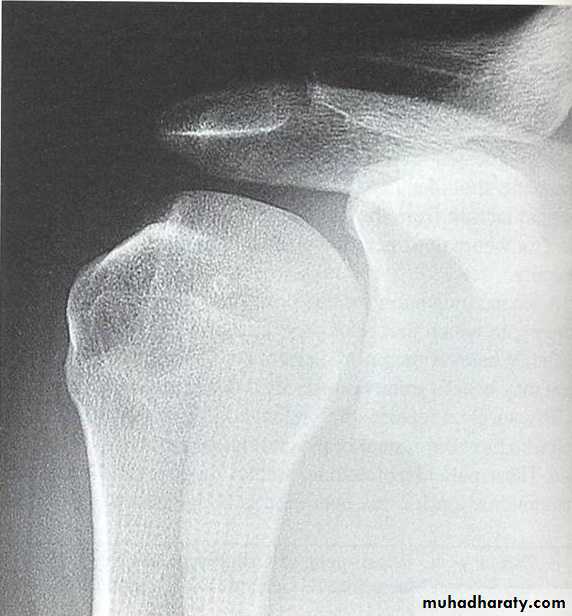

The lateral outline of the shoulder is flattened

XR

AP

Scapular lateral

Axillary lateral